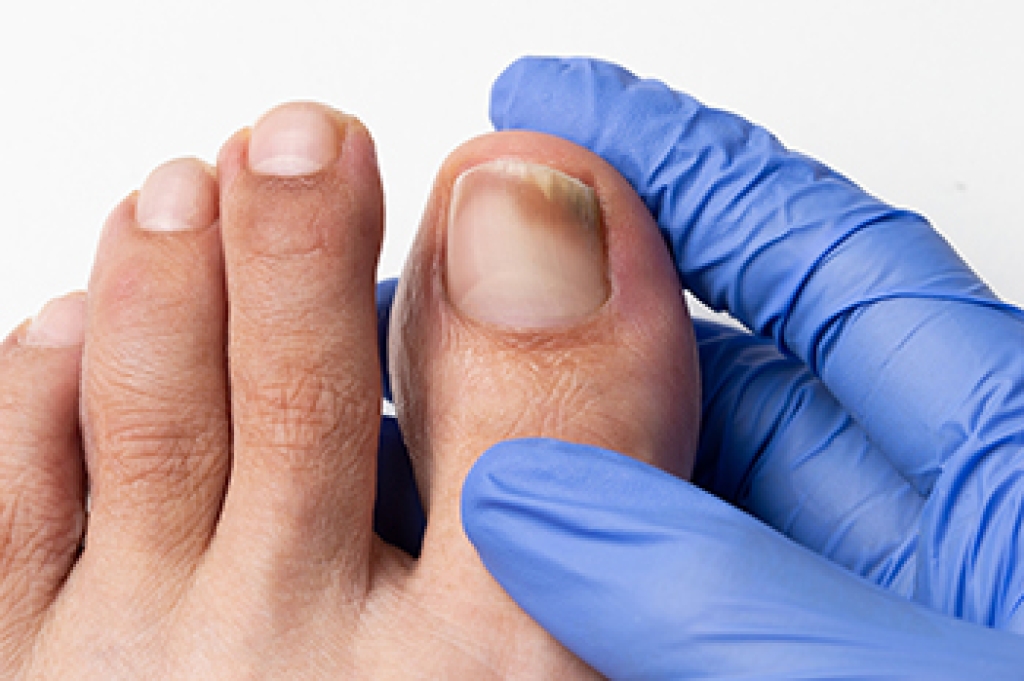

Osteoarthritis in the big toe, often called hallux rigidus, occurs when the cartilage in the joint at the base of the toe gradually wears down. This joint plays an important role in walking, especially during push-off. Over time, repeated stress, prior injury, or inherited foot structure can lead to joint damage. Patients often notice pain and stiffness in the big toe, particularly when bending it upward. The joint may appear swollen, enlarged, or develop a visible bump from bone spurs. Shoes with a narrow toe box can make the discomfort worse, and walking or running may become difficult. As the condition progresses, motion in the joint becomes limited and the pain may increase. A podiatrist can evaluate the joint, obtain imaging if needed, and determine the stage of arthritis. Treatment may include shoe modifications, custom orthotics, anti-inflammatory care, and targeted exercises. In advanced cases, surgical options may be discussed. If you have osteoarthritis in the big toe, it is suggested that you make an appointment with a podiatrist for proper evaluation and care.

What Causes Toe Pain?

Most severe toe pain is caused due to a sports injury, trauma from dropping something heavy on the toe, or bumping into something rigid. Other problems can develop over time for various reasons.

Toe pain can be caused by one or more ailments. The most common include:

In many cases the cause of toe pain is obvious, but in others, a podiatrist may want to use more advanced methods to determine the problem. These can range from simple visual inspections and sensation tests to X-rays and MRI scans. Prior medical history, family medical history, and any recent physical traumatic events will all be taken into consideration for a proper diagnosis.

Treatments for toe pain and injuries vary and may include shoe inserts, padding, taping, medicines, injections, and in some cases, surgery. If you believe that you have broken a toe, please see a podiatrist as soon as possible.